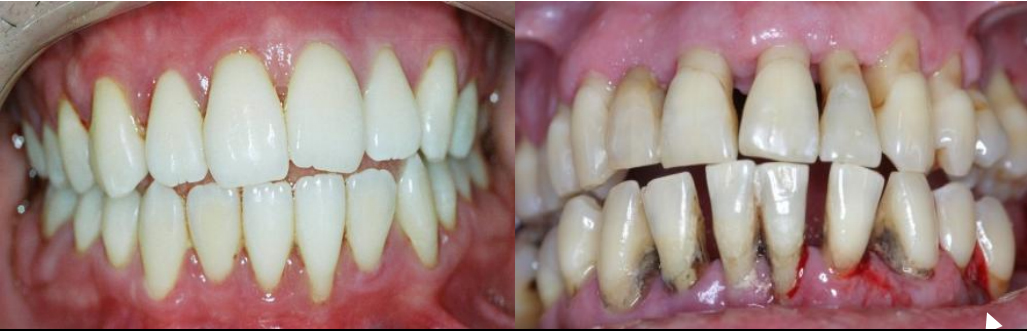

A periodontite agressiva juvenil é uma doença gengival séria que afeta jovens. Ela causa destruição rápida do osso e dos tecidos que sustentam os dentes. O diagnóstico precoce é crucial para evitar a perda dentária.

A periodontite agressiva juvenil, quando não tratada, pode trazer sérias consequências para a saúde bucal. Por isso, a limpeza profissional não é só um cuidado estético, é a base para o controle dessa condição. Dentistas e higienistas têm as ferramentas e o conhecimento para remover aquela placa bacteriana e o tártaro que o dia a dia em casa não alcança. É um passo fundamental para frear a progressão da doença.

Nesse tratamento, o foco é a remoção minuciosa das bactérias. Os profissionais utilizam instrumentos específicos para limpar profundamente as bolsas periodontais, que são aquelas espaços que se formam entre o dente e a gengiva quando a doença avança. O objetivo é criar um ambiente bucal mais saudável, onde a gengiva possa começar a se recuperar e a inflamação diminua. É um trabalho delicado, que exige precisão.

Vamos falar sério agora sobre periodontite agressiva juvenil. Se você ou alguém que você conhece está lidando com isso, sabe que é um assunto delicado. Basicamente, quando a doença periodontal avança e a inflamação já causou perdas ósseas significativas, a cirurgia pode ser o caminho. É aquela situação em que a limpeza profunda que fazemos não consegue mais alcançar as bactérias mais problemáticas.

Eu já vi casos onde a gengiva se retrai muito, deixando a raiz do dente exposta. Isso não é só questão estética, viu? Aumenta a sensibilidade e o risco de cáries nessa área. A cirurgia periodontal entra para tentar recuperar o suporte dos dentes, removendo as bolsas periodontais e, em alguns casos, até regenerando o osso perdido. É um procedimento para quando outras abordagens não foram suficientes, entende?